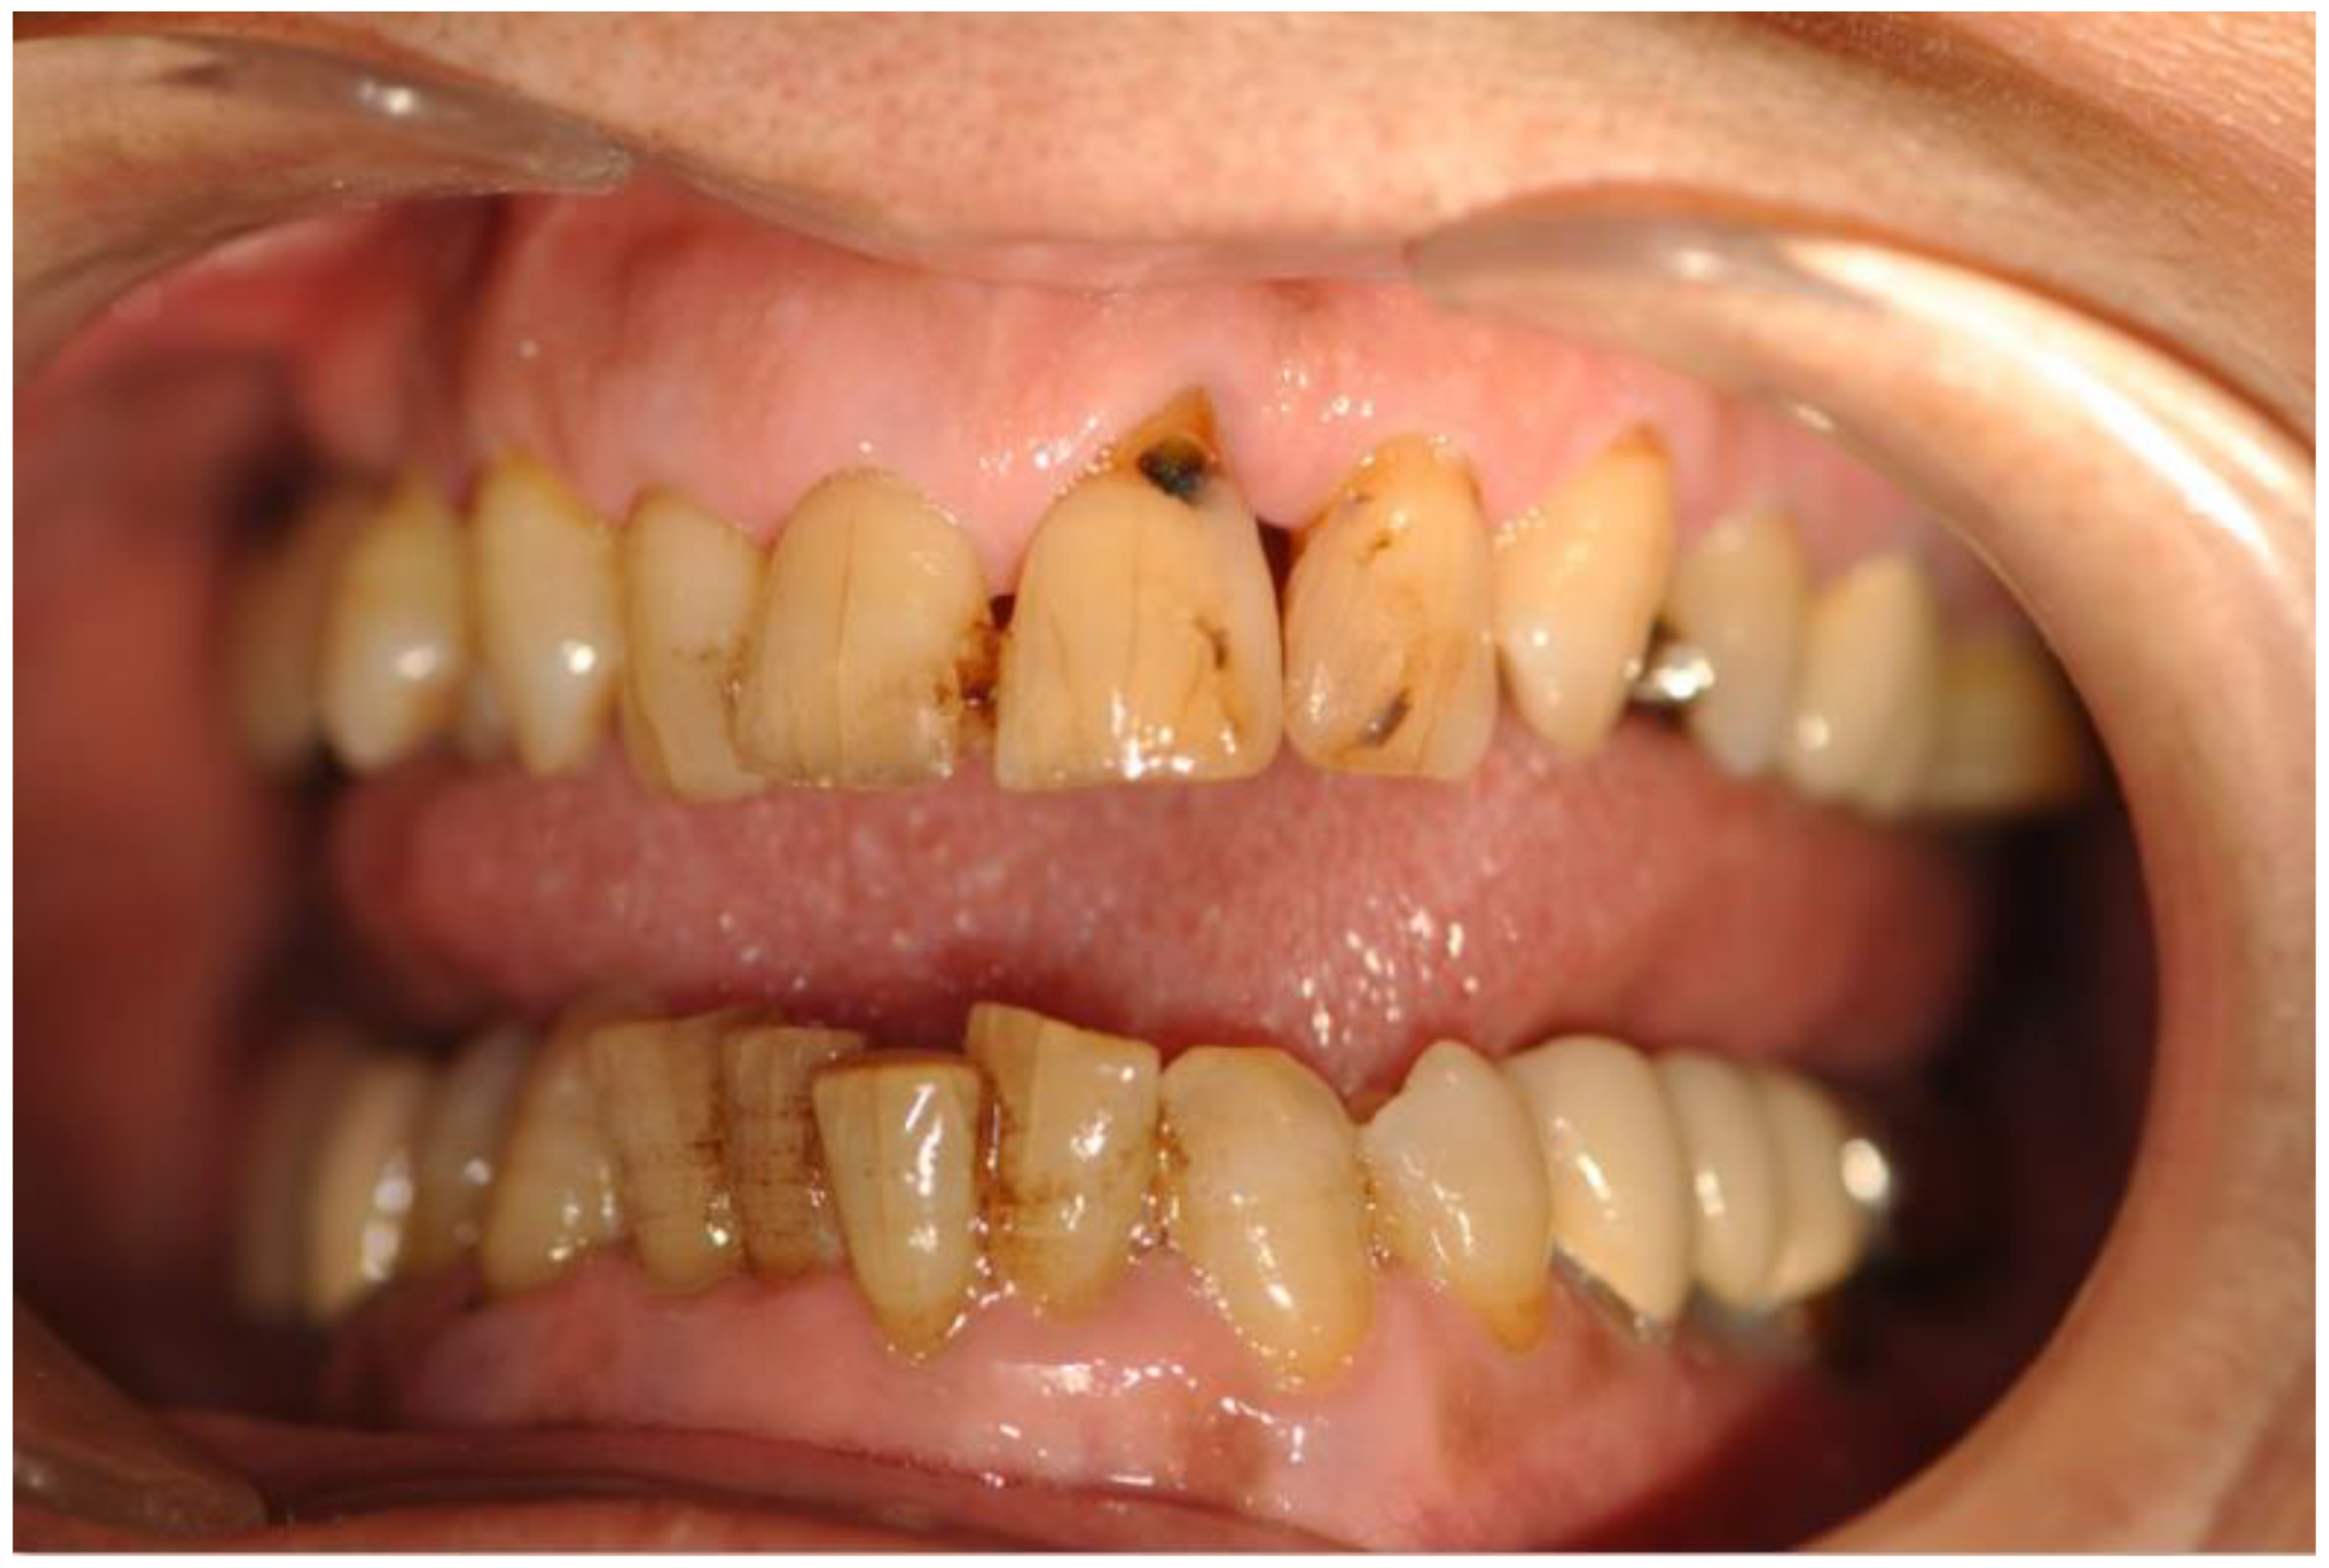

Dental caries form when acids produced by bacteria in the mouth erode dentin, causing damage to tooth structure or attachment, which can make gums bleed. They are the most common chronic oral disease in adults, affecting around 60% of adults over the age of 50. Dental health is part of oral health [], including the state of oral tissues as well as factors that can affect oral health. Dental plaque is initially a soft, thin film. Soft plaque turns into hard plaque, which cannot be easily removed by brushing, via mineralization with calcium, phosphate, and other minerals []. Over time, caries cause holes, destroy the tooth, and increase the risk of further damage, including tooth loss (Figure 1).

Figure 1.

Caries in teeth.